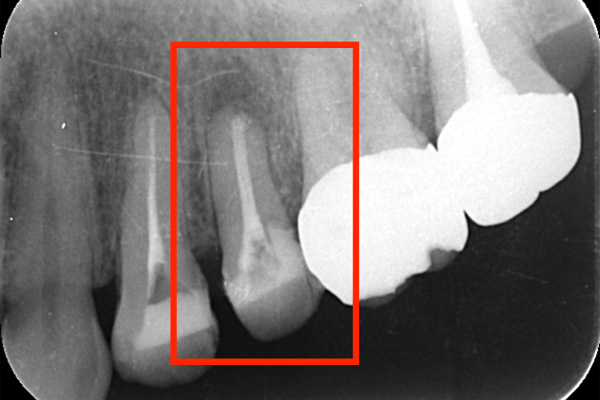

左のレントゲンでは破折したかどうかはわからないが、虫歯になっている部分をとっていくと歯が割れているのがはっきりとわかりました。

歯が割れるケースで多いのが金属の土台(メタルコア)が入っている場合です。特に根の中に長いものが入っていると、歯を割る力が強くかかるため、割れることが多いです。

破折に気づいてからは、抜歯を行い、インプラントを入れてまた噛める様にしていきました。レントゲンでも破折がわからない時があります。そんな時はCTやマイクロスコープを使うとわかることが多いのです。